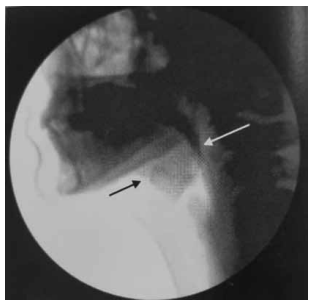

Observe, a seguir, a imagem de uma videofluoroscopia.

(Magalhães e Magnoni, Disfagia orofaríngea no adulto e no ambiente hospitalar)

Assinale a alternativa que corretamente a caracteriza.